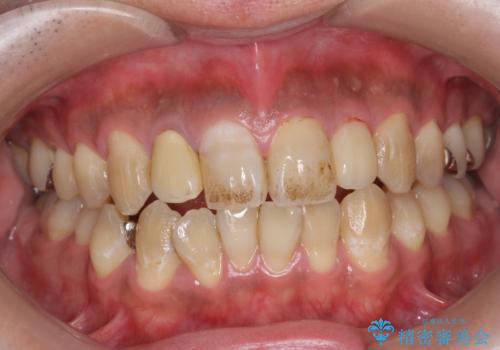

PMTC(歯科医院での専門的クリーニング)でステインを除去し白くきれいな歯に!

- コーヒーによる着色を気にされ、来院されました。

歯の着色だけでなく、汚れも除去し歯の表面がツルツルになったと喜んでいただけました。